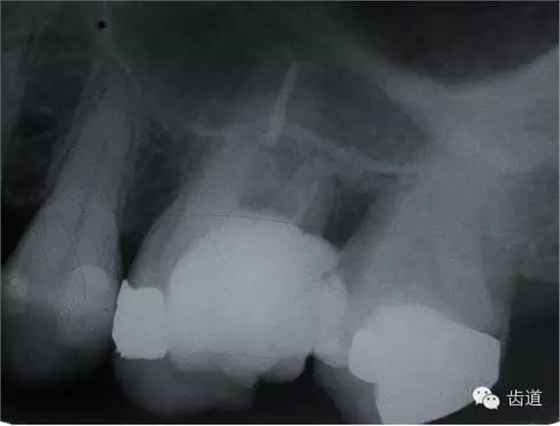

左下7根充后下唇麻木

左下5根管預(yù)備后下唇麻木